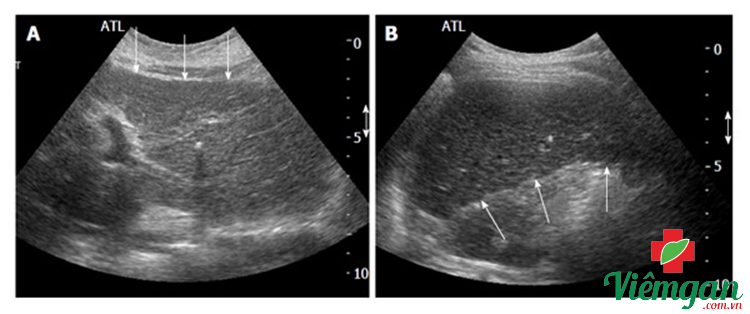

Hình ảnh siêu âm xơ gan

Dưới đây là một vài hình ảnh siêu âm xơ gan mang tính chất tham khảo:

Hình ảnh 1

- Màn hình A: Chụp cắt lớp thượng vị cho thấy thùy trái của gan (tại mũi tên) có bề mặt không đều, đồng thời kết cấu phản âm nhu mô thô.

- Màn hình B: Chụp cắt lớp dưới sườn cho thấy bờ dưới của thùy gan phải có bề mặt không đều (quan sát chỗ mũi tên).